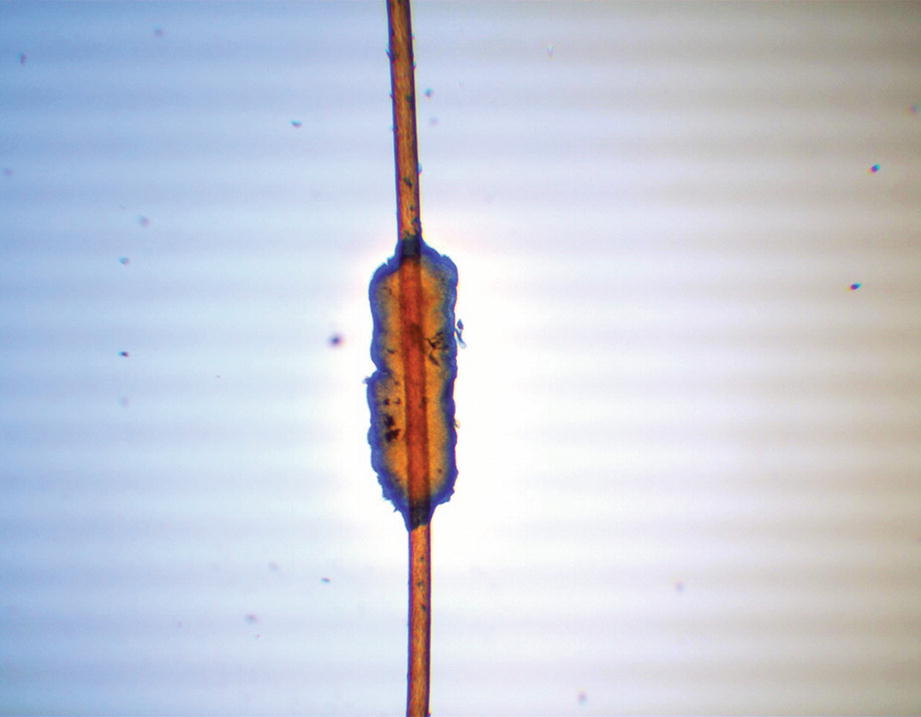

Trichomycosis (lactophenol cotton blue 40×)